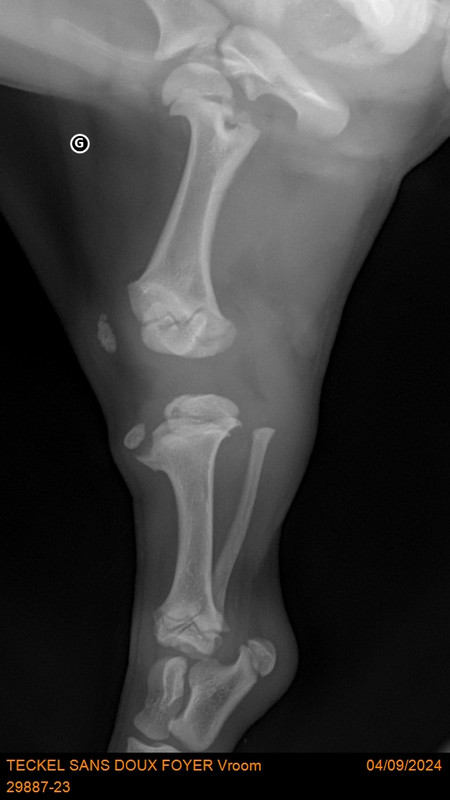

[Image: 29887-23-TECKEL-SANS-DOUX-FOYER-Vroom-20788.jpg]

[Image: 29887-23-TECKEL-SANS-DOUX-FOYER-Vroom-20789.jpg]

[Image: 29887-23-TECKEL-SANS-DOUX-FOYER-Vroom-20790.jpg]

Patte arrière gauche [Image: chien-2010-32.gif]

Sur la deuxième radios les 2 cotés ne sont pas identiques. C’est là le problème ?

Oui, son problème de rotule au genou se répercute sur la hanche, d’où la nécessité de l'opérer de toute urgence sinon il risque une dysplasie de la hanche. Et aussi ne pas grandir normalement !